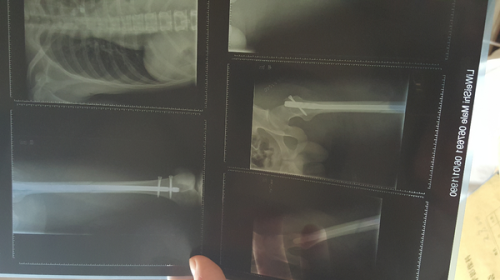

全身90针多处骨折+肺部破洞+颅脑严重受损,现在全力康复中。

[废话]感谢大家的关心,诚意附上上周照片*^O^*